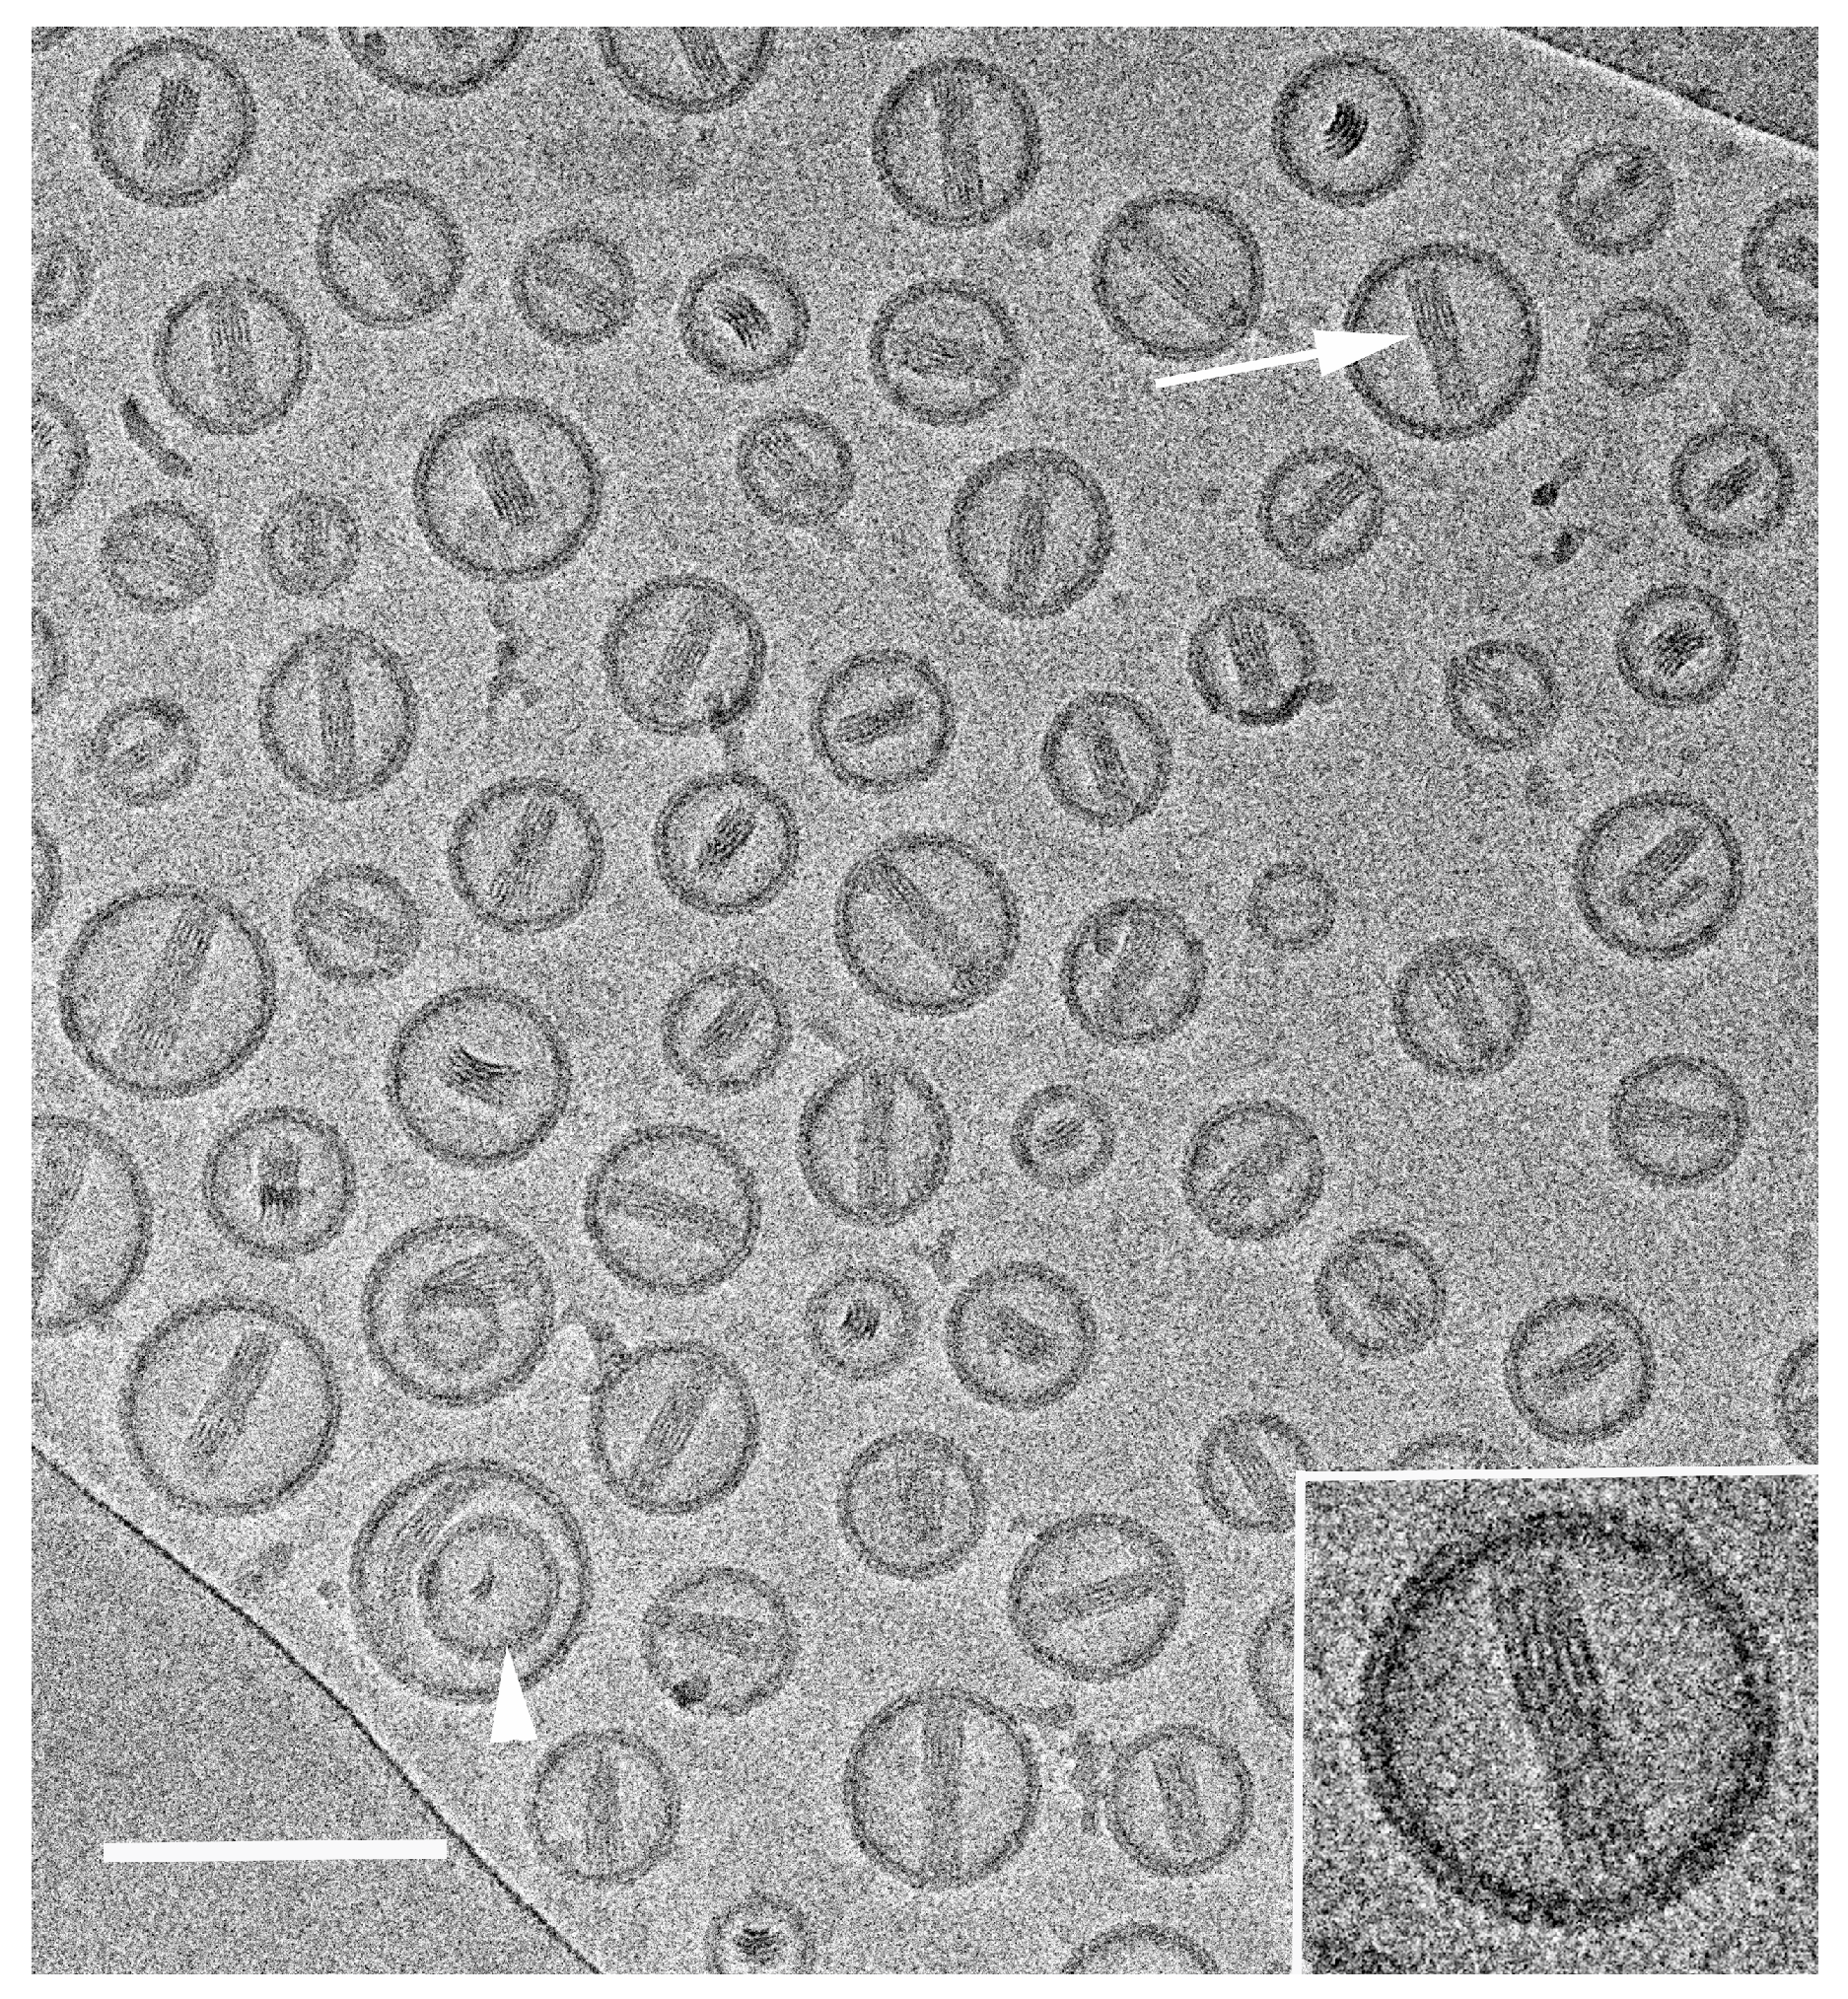

- Barenholz, Y. Doxil®–The first FDA-approved nano-drug: Lessons learned. J. Control. Release 2012, 160, 117–134. [Google Scholar] [CrossRef] [PubMed]

- Yaari, Z.; Da Silva, D.; Zinger, A.; Goldman, E.; Kajal, A.; Tshuva, R.; Barak, E.; Dahan, N.; Hershkovitz, D.; Goldfeder, M.; et al. Theranostic barcoded nanoparticles for personalized cancer medicine. Nat. Commun. 2016, 7, 13325. [Google Scholar] [CrossRef] [Green Version]